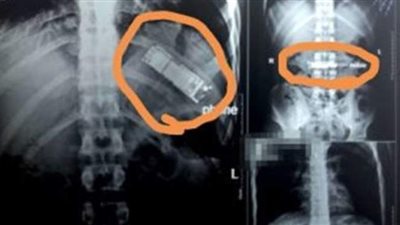

موبيل في معدة مريض

"بطن المصريين مش بتهضم الزلط وبس".. العثور على موبيل داخل معدة مريض.. والفوط والمقصات والمسامير الأبرز

نجحت عمليات جراحية في استخراج أصعب الأشياء من أمعاء مواطنين